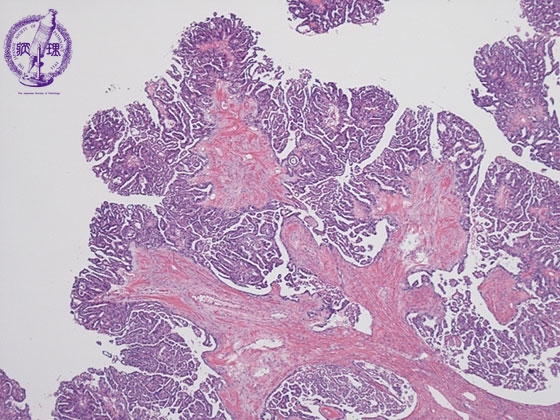

卵巣漿液性嚢胞腺癌ミクロ像(HE弱拡大)

ミクロ像(HE弱拡大):卵巣漿液性嚢胞腺癌。比較的小型で立方状の癌細胞が線維性の間質(黄色点線)を伴いながら乳頭状に増殖している。